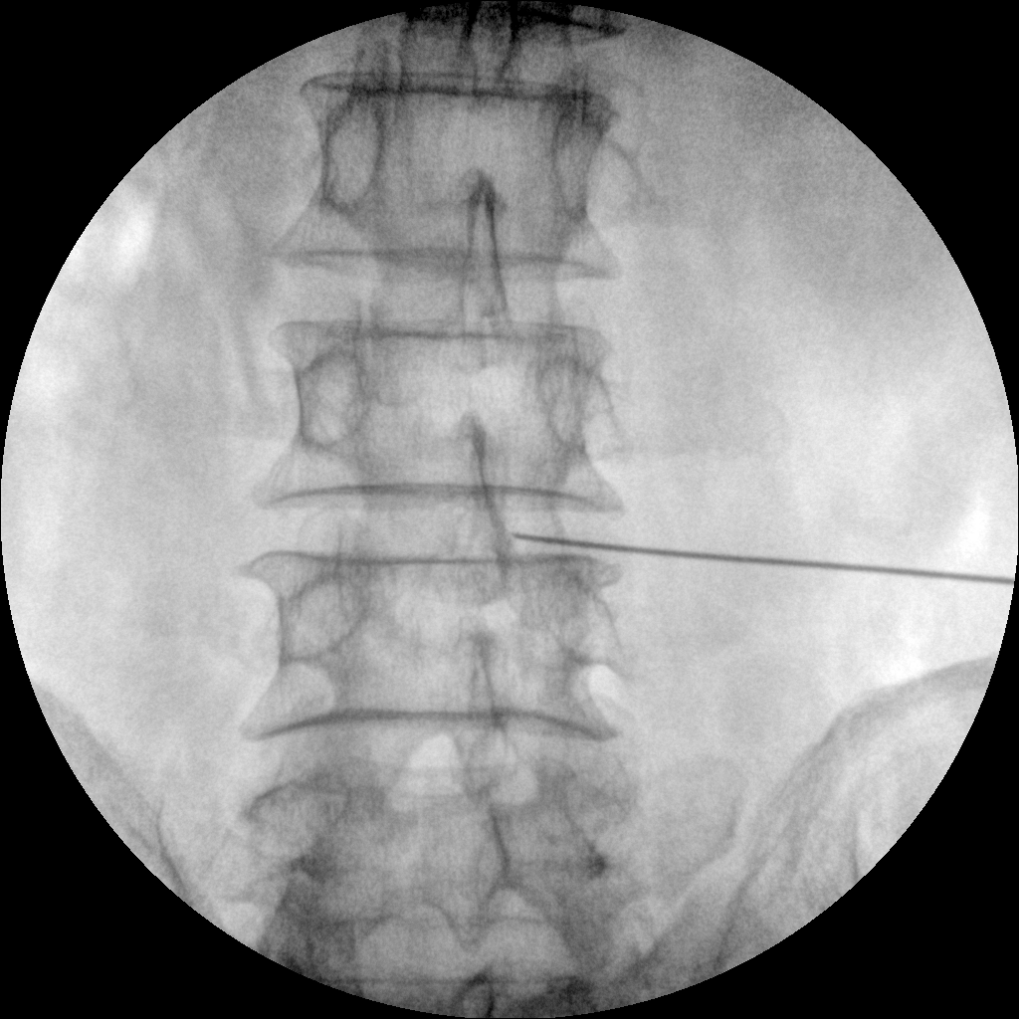

PLX112B 系列高频移动式手术X射线机

●经典影像工作站,可隔室操作避免辐射●全数字化百万像素影像系统,图像清晰●灵活的C臂机架设计,满足临床大范围运动●临床功能丰富,具备脉冲控制、数字摄影、自动透视等●具备手持控制器,远离主机也可自由控制